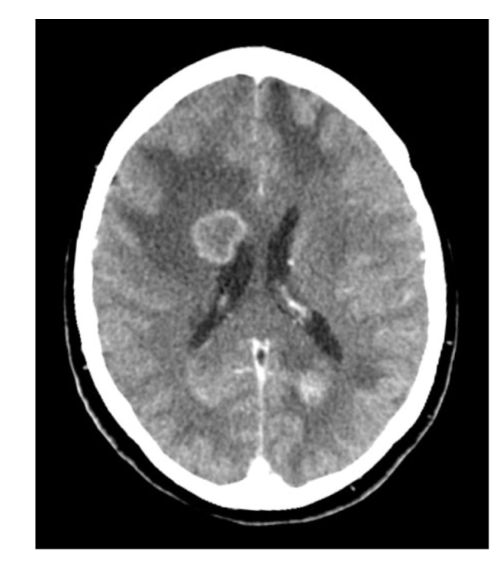

What is the protocol + pathology?

• CT non con brain

• Intraparenchymal

haemorrhage: brain bleed within the brain parenchyma

• Hyperattenuating mass posteriorly in the occipital lobe

• Midline shift

• Adjacent oedema.